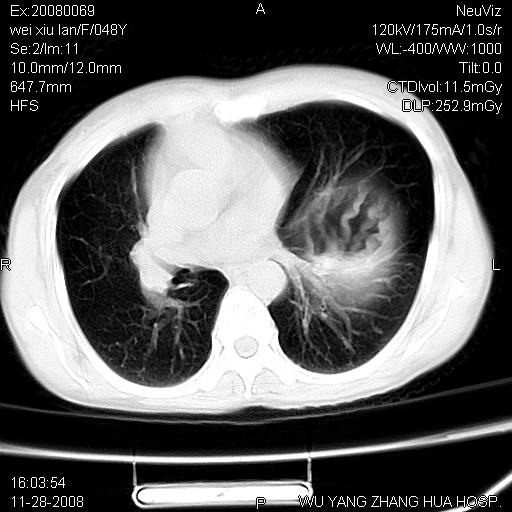

标题: CT16847:女,48岁,咳嗽,发热两日,平常偶有上腹部不适。 [打印本页]

标题: CT16847:女,48岁,咳嗽,发热两日,平常偶有上腹部不适。

能否考虑食管裂孔疝?请老师们多多指教。

胃、脾脏及部分肠管明显升高,并压迫心脏移位,

首先考虑:左侧膈疝。

左侧胸腔内见胃肠及脾脏影

支持膈疝

支持左侧膈疝,心脏受压右移.

左下肺不张、膈膨升,胸腔胃

这个是左侧膈膨升伴不完全性胃翻转,手术将松弛的左横膈膜折叠缝合即解决问题。

2.左下肺炎性改变

左膈顶及肋膈角均上移,膈面光滑,考虑左膈肌麻痹